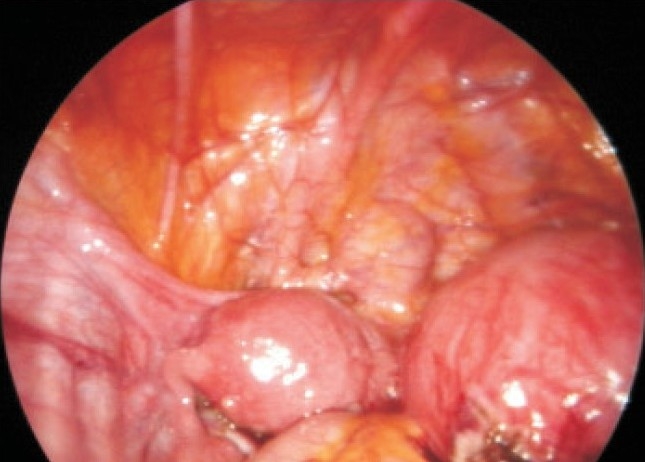

未婚女孩重度痛经,因双侧子宫内膜瘤剖腹手术,经达那唑和GnRHa Depo注射治疗三年多。腹腔镜检查发现她有一个大的、不相通的、功能不全的角伴同侧肾发育不全。腹腔镜下对原始角的切除使疑似子宫内膜异位瘤得到了很大的缓解,这并不是她剧烈疼痛的原因。

An unmarried girl with severe dysmenorrhea had laparotomy for bilateral endometriomas, later treated with danazol and GnRHa Depo injection for more than three years. On laparoscopy she had a large, noncommunicating, functioning rudimentary horn with ipsilateral renal agenesis. Laparoscopic excision of the rudimentary horn gave major relief from the suspected endometrioma, which was not the cause of her severe pain.